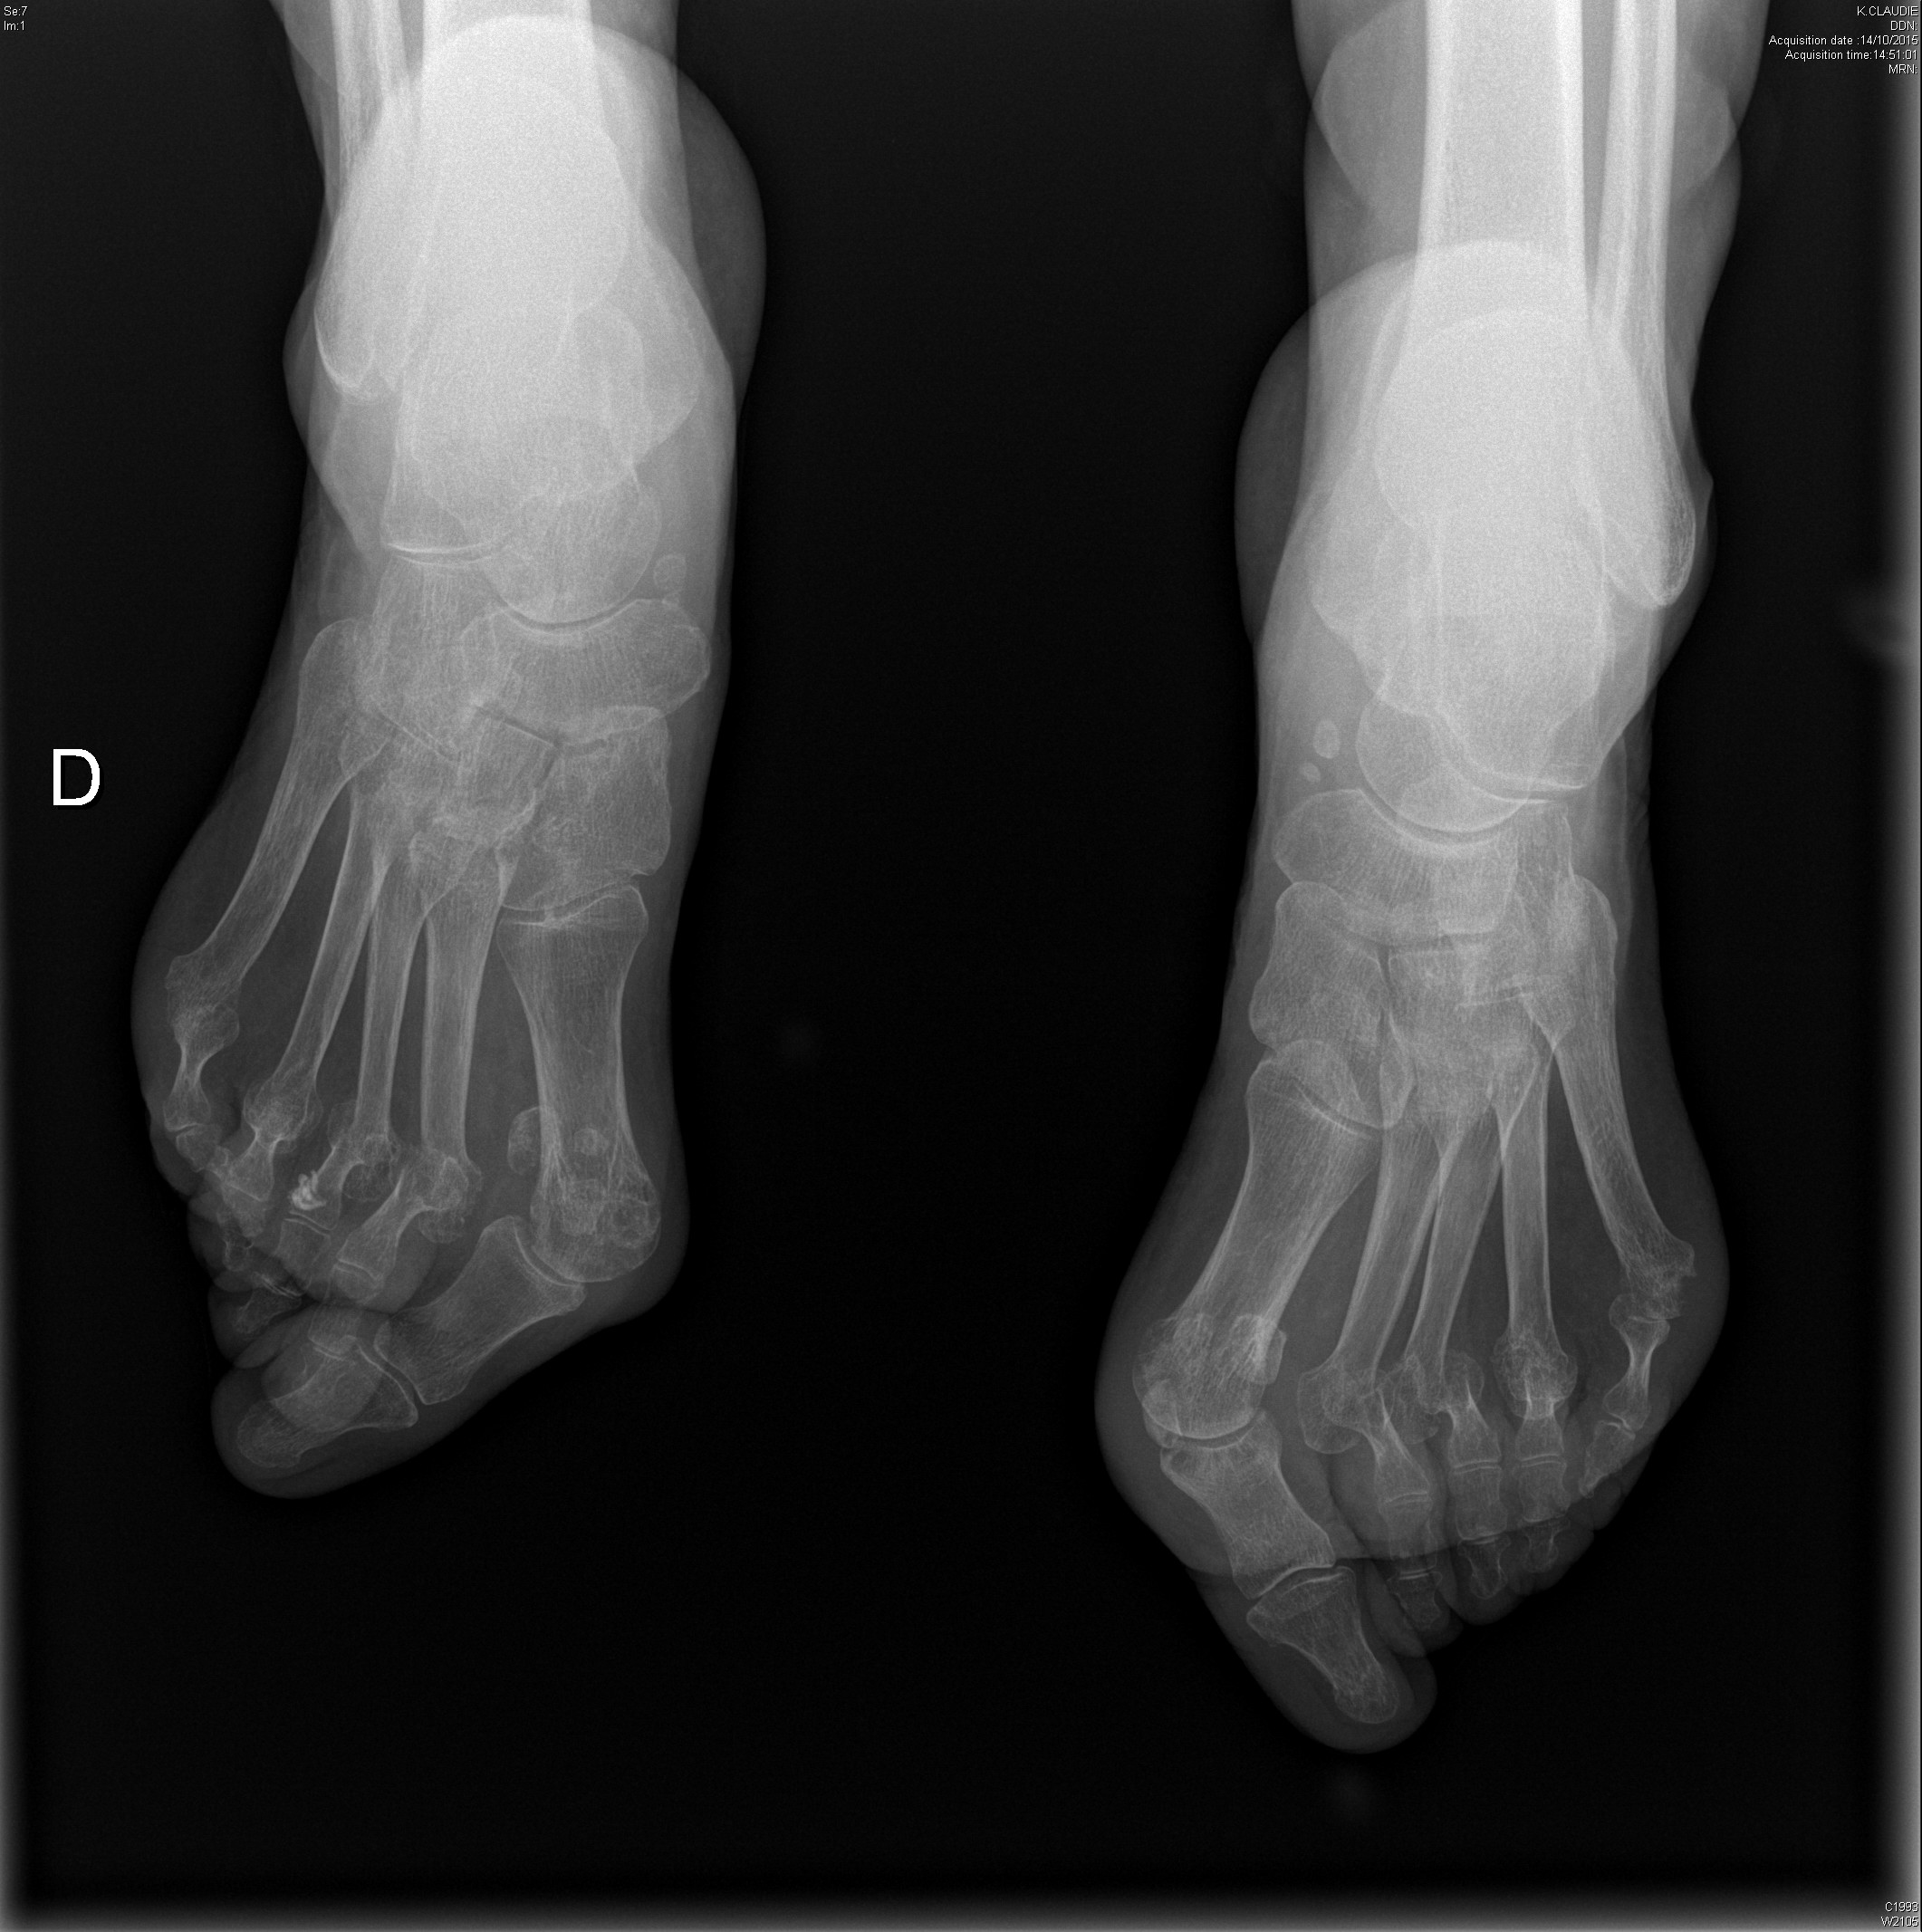

Polyarthrite rhumatoïde séropositive, sévèrement érosive aux pieds